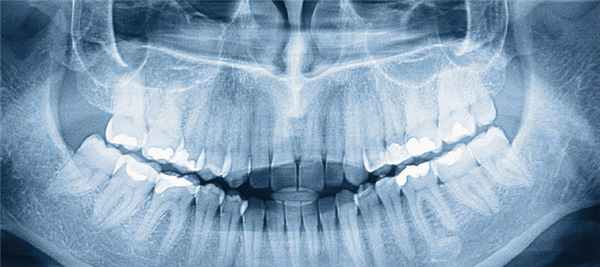

Аномалии зубов - различного рода морфологические и функциональные отклонения от нормального количества, размера, формы, цвета, положения, сроков прорезывания, структуры тканей зубов. Аномалии зубов сопровождаются деформацией челюстно-лицевой области, неправильным прикусом, затруднениями при откусывании и пережевывании пищи, дефектами речи, эстетическими недостатками. Диагностика аномалий зубов включает внутриротовую рентгенографию, проведение и анализ ТРГ, панорамную рентгенографию, ОПТГ, томографию ВНЧС, снятие слепков, изготовление и измерение диагностических моделей челюстей, электромиографию и др. Способ лечения определяется видом аномалии зубов.

Для уточнения аномалий зубов, определения плана лечения и его контроля осуществляется рентгенографическое обследование:внутриротовая рентгенография, панорамная рентгенография челюстей, ортопантомография, томография ВНЧС и пр. С целью оценки функционального состояния мышц лица выполняется электромиография.

Рентген зубов: виды снимков, вред, противопоказания

Одним из традиционных и весьма популярных диагностических способов в стоматологической отрасли является рентгенологическое обследование. Что видно на рентгене зубов? Дентальный снимок позволяет определить степень поражения твердых тканей, выявить скрытый кариес, оценить качество ранее проведенного лечения зубов, а также своевременно диагностировать очаги воспаления в периодонте.

Снимки рентгена позволяют наглядно продемонстрировать не только состояние костных тканей, но и определить множество негативных изменений. Это крайне важно для постановки точного диагноза и определения соответствующей схемы лечения.

Это один видов исследования, пользующийся достаточным спросом. С помощью данной методики удается получить изображение абсолютно всех челюстей и зубов.

Что дает панорамный снимок зубов?

Полученное изображение дает специалисту следующие сведения: